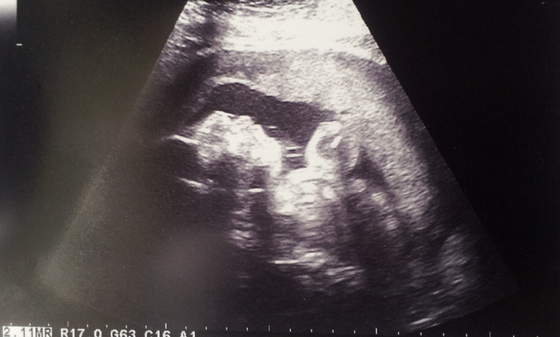

To jest Mateusz drugi do wyjscia z kciukiem w buzi

20120922_160614.jpg

A to Filip z mamusinym noskiem, biedactwo ladniutkie po mamusi ale brzydki profil tez po mamusi, nie bedziemy mu robic zdjec profilu :PPP